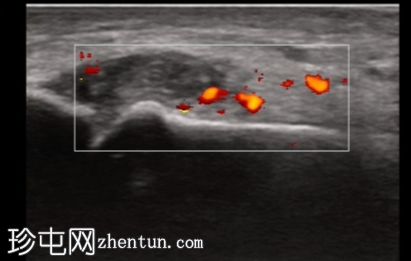

纵轴切面

第一跖趾关节纵轴切面

关节积液伴轻度滑膜增生。高回声不规则沉积物,符合尿酸钠晶体沉积的典型表现。彩色多普勒成像显示滑膜充血活跃,符合急性炎症活动。